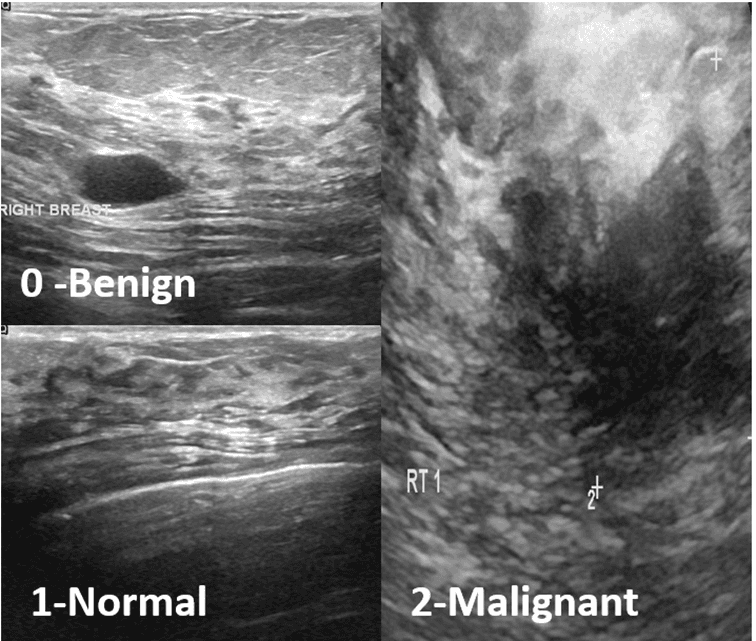

Abstract: Breast Cancer is one of the most life-threatening diseases for women around the world. In 2022, breast cancer caused 670,000 deaths globally in 2022. Early detection of this disease is extremely important to avoid death. For diagnosing this image ultrasound is a safe approach since ultrasound don’t have any risk of radiation. That is why in this study we have decided to use ultrasound image dataset. In this study, we will utilize different deep learning models to classify breast cancer from ultrasound images. There are 3 classes in the dataset that have been used; benign, malignant and Normal. The dataset has 780 images along with their mask. DenseNet201 and ResNet50 these two deep learning models were employed in this research. The models were trained using two different methods and for both methods dataset was split into train 80%,validation 10% and test 10%. At first, the models were trained using only the images. In second method, those masks that were in the dataset were overlaid with images. Then models were then trained with those overlaid image. Hyper parameter tuning was done for each method. Data augmentation was done when training the models for both techniques as well. Models’ performance when training with only raw images were not up to expectations and the accuracy was around only 80%. But when trained with overlaid images their performance become a lot better. Both models achieved an accuracy of 97% accuracy when trained with overlayed images. The research perfectly portrays the effectiveness of manually created mask.